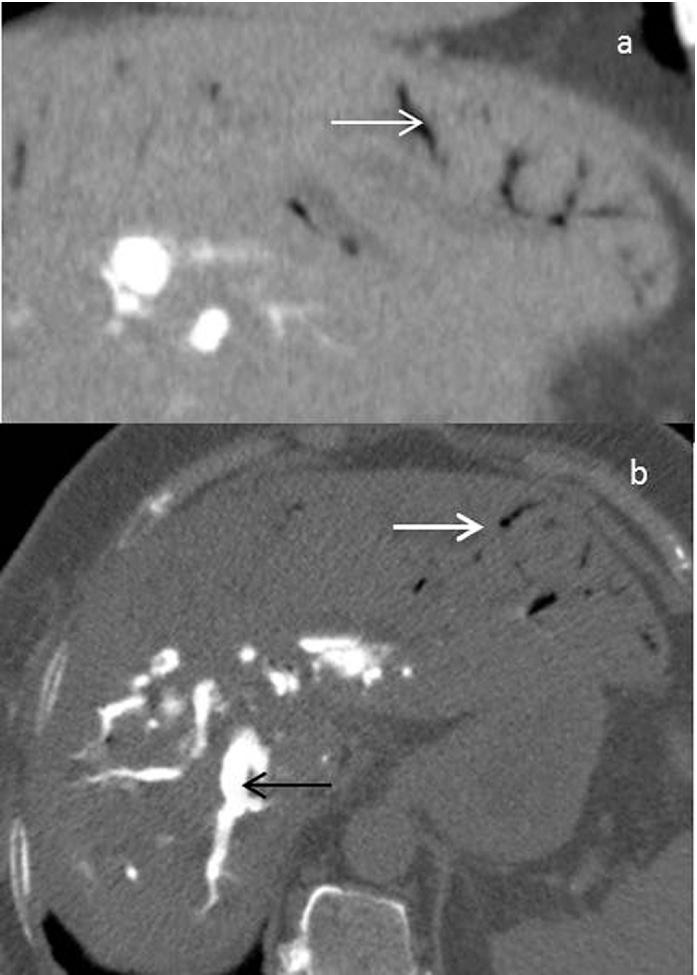

Etiologies were mesenteric infarction (n=5), sigmoid diverticulitis (n= 1), septic shock (n=1), postoperative peritonitis (n=1), acute pancreatitis (n=1), iatrogenic cause (n=3) and idiopathic after a laparotomy (n=1). The outcome was fatal in for 6 patients. Abundance of HPV was expressed in total number of hepatic segments involved. The involvement of 3 or more segments was a sensitive sign for lethal outcome with high sensitivity (100%) but it was not specific (50%). Negative predictive value of this sign was 100% (p≤0.005). Positive predictive value of PI for death was 100% (p≤0.001).

The first etiology radiologists should look for in front of HPVG involving more than 3 hepatic segments and associated with PI is intestinal necrosis which announces a poor prognosis. This study shows that outside of shock situations, HPVG involving 2 or less hepatic segments without PI predicts a good outcome.

病因包括肠系膜梗死(n = 5)、乙状结肠憩室炎(n = 1)、感染性休克(n = 1)、术后腹膜炎(n = 1)、急性胰腺炎(n = 1)、医源性原因(n = 3)和剖腹术后特发性(n = 1)。6例患者预后为致命。HPV的丰度以受累肝段总数表示。3个或更多肝段受累是致命结局的敏感征象,敏感性高(100%)但不具有特异性(50%)。该征象的阴性预测值为100%(p≤0.005)。PI对死亡的阳性预测值为100%(p≤0.001)。

对于累及3个以上肝段且伴有PI的HPVG,放射科医生首先应寻找的病因是肠坏死,这预示着预后不良。本研究表明,在非休克情况下,累及2个或更少肝段且无PI的HPVG预示预后良好。